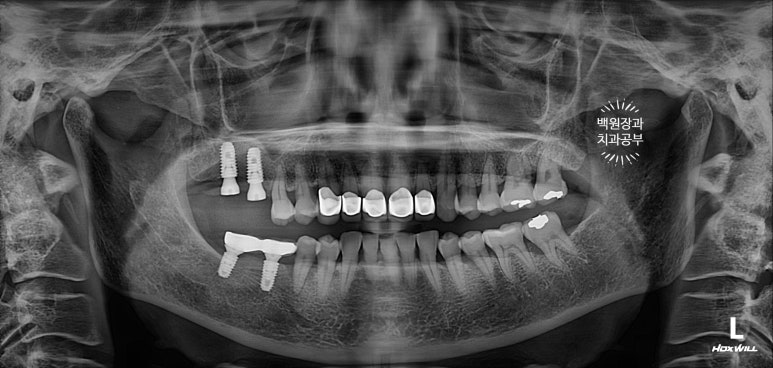

임플란트 2차 수술을 마칠 당시, 상악동 뼈이식술을 했던 부위가 훨씬 확연하게 드러나는 것을 보실 수 있을거에요.

짜잔! 이렇게 임플란트까지 아주 예쁘게 마무리가 되었었답니다.

3년이 지나니 상악동 뼈이식술을 했던 곳은 이제 거의 내 뼈와 하나가 된 것처럼 예쁘게 성숙된 모습을 보여주고 있고, 앞니 지르코니아 크라운은 꼼꼼히 관리해주신 덕분에 충치 하나 없이 신경치료 하지 않았음에도 아주 잘~ 쓰고 있는 모습을 확인할 수 있었습니다!